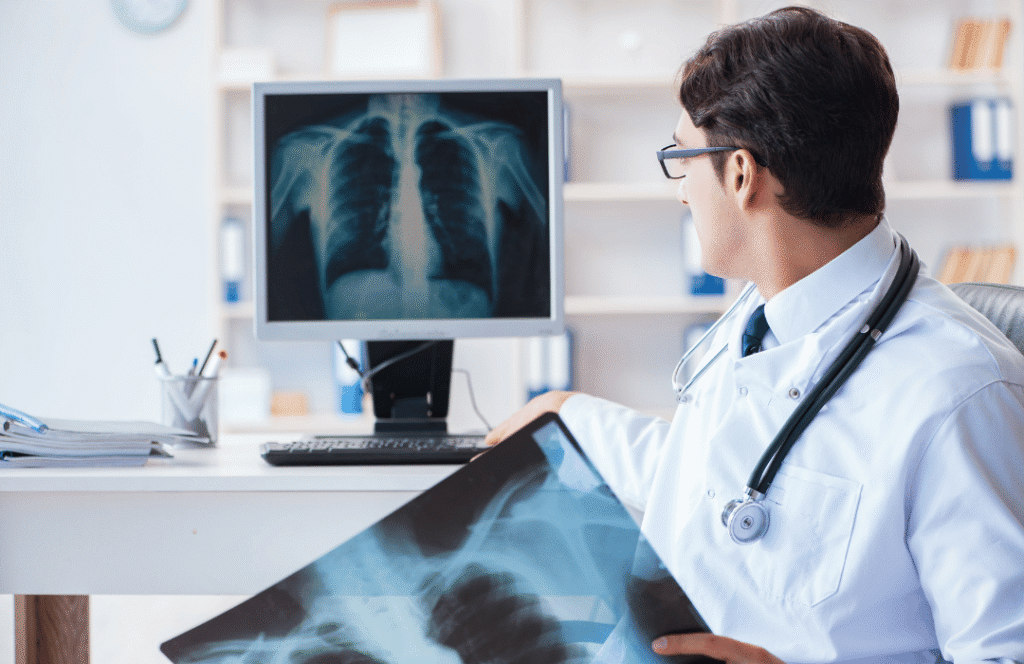

Diagnostic Center

Challenge

No personal brand and poor digital reach.

Solution

Personal branding, healthcare content marketing, and AI-based patient engagement.

Results

✔ Strong doctor brand authority

✔ Increased online consultations

✔ Improved patient retention